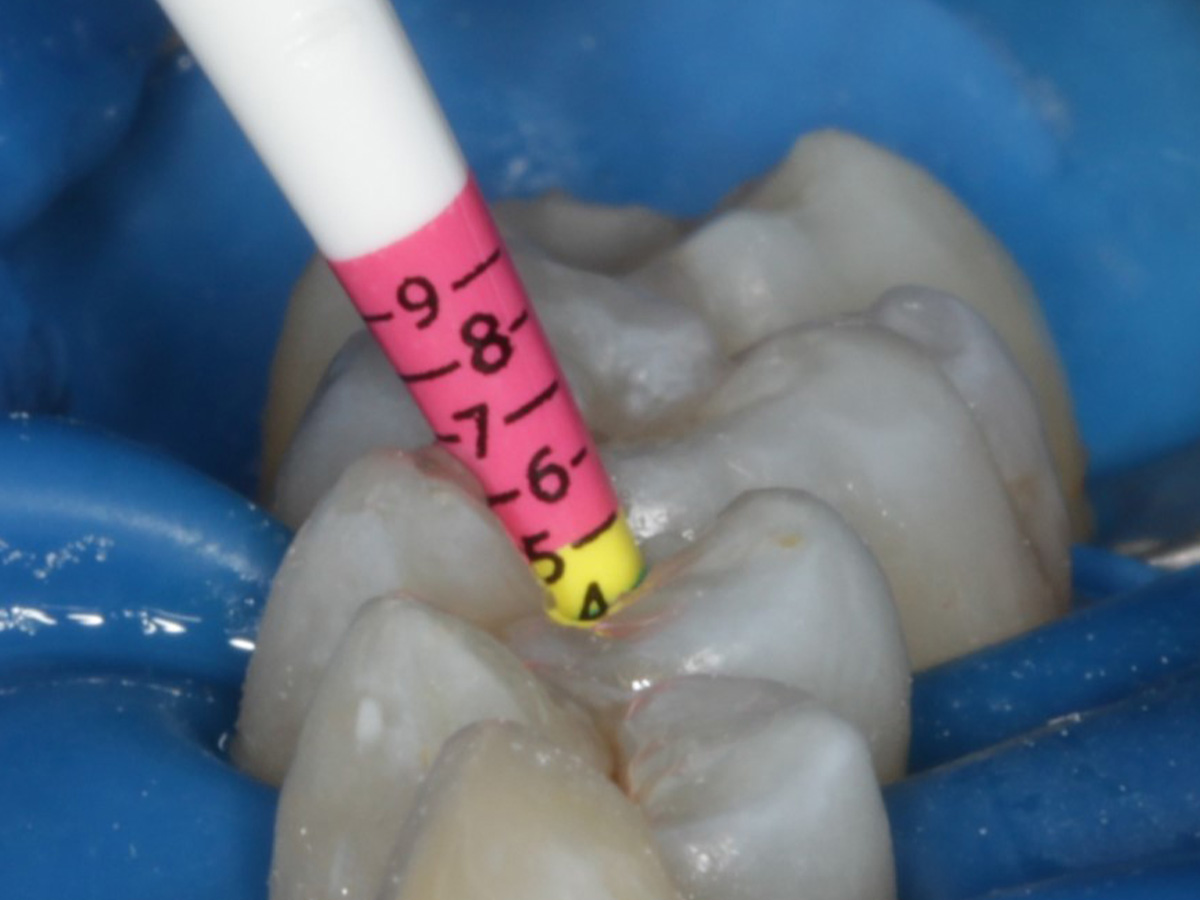

Abbildung 9

Height Indicator vor Auswahl der passenden Evolve Matrize